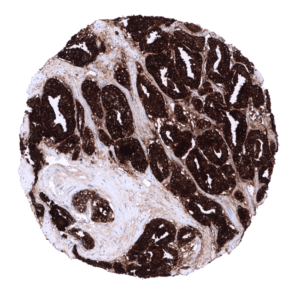

Positive control = Prostate: The epithelial cells of the prostate glands must show a strong cytoplasmic staining. Due to leakage of the antigen in the vicinity of the prostate glands, adjacent stroma cells may display a weak to moderate staining reaction.